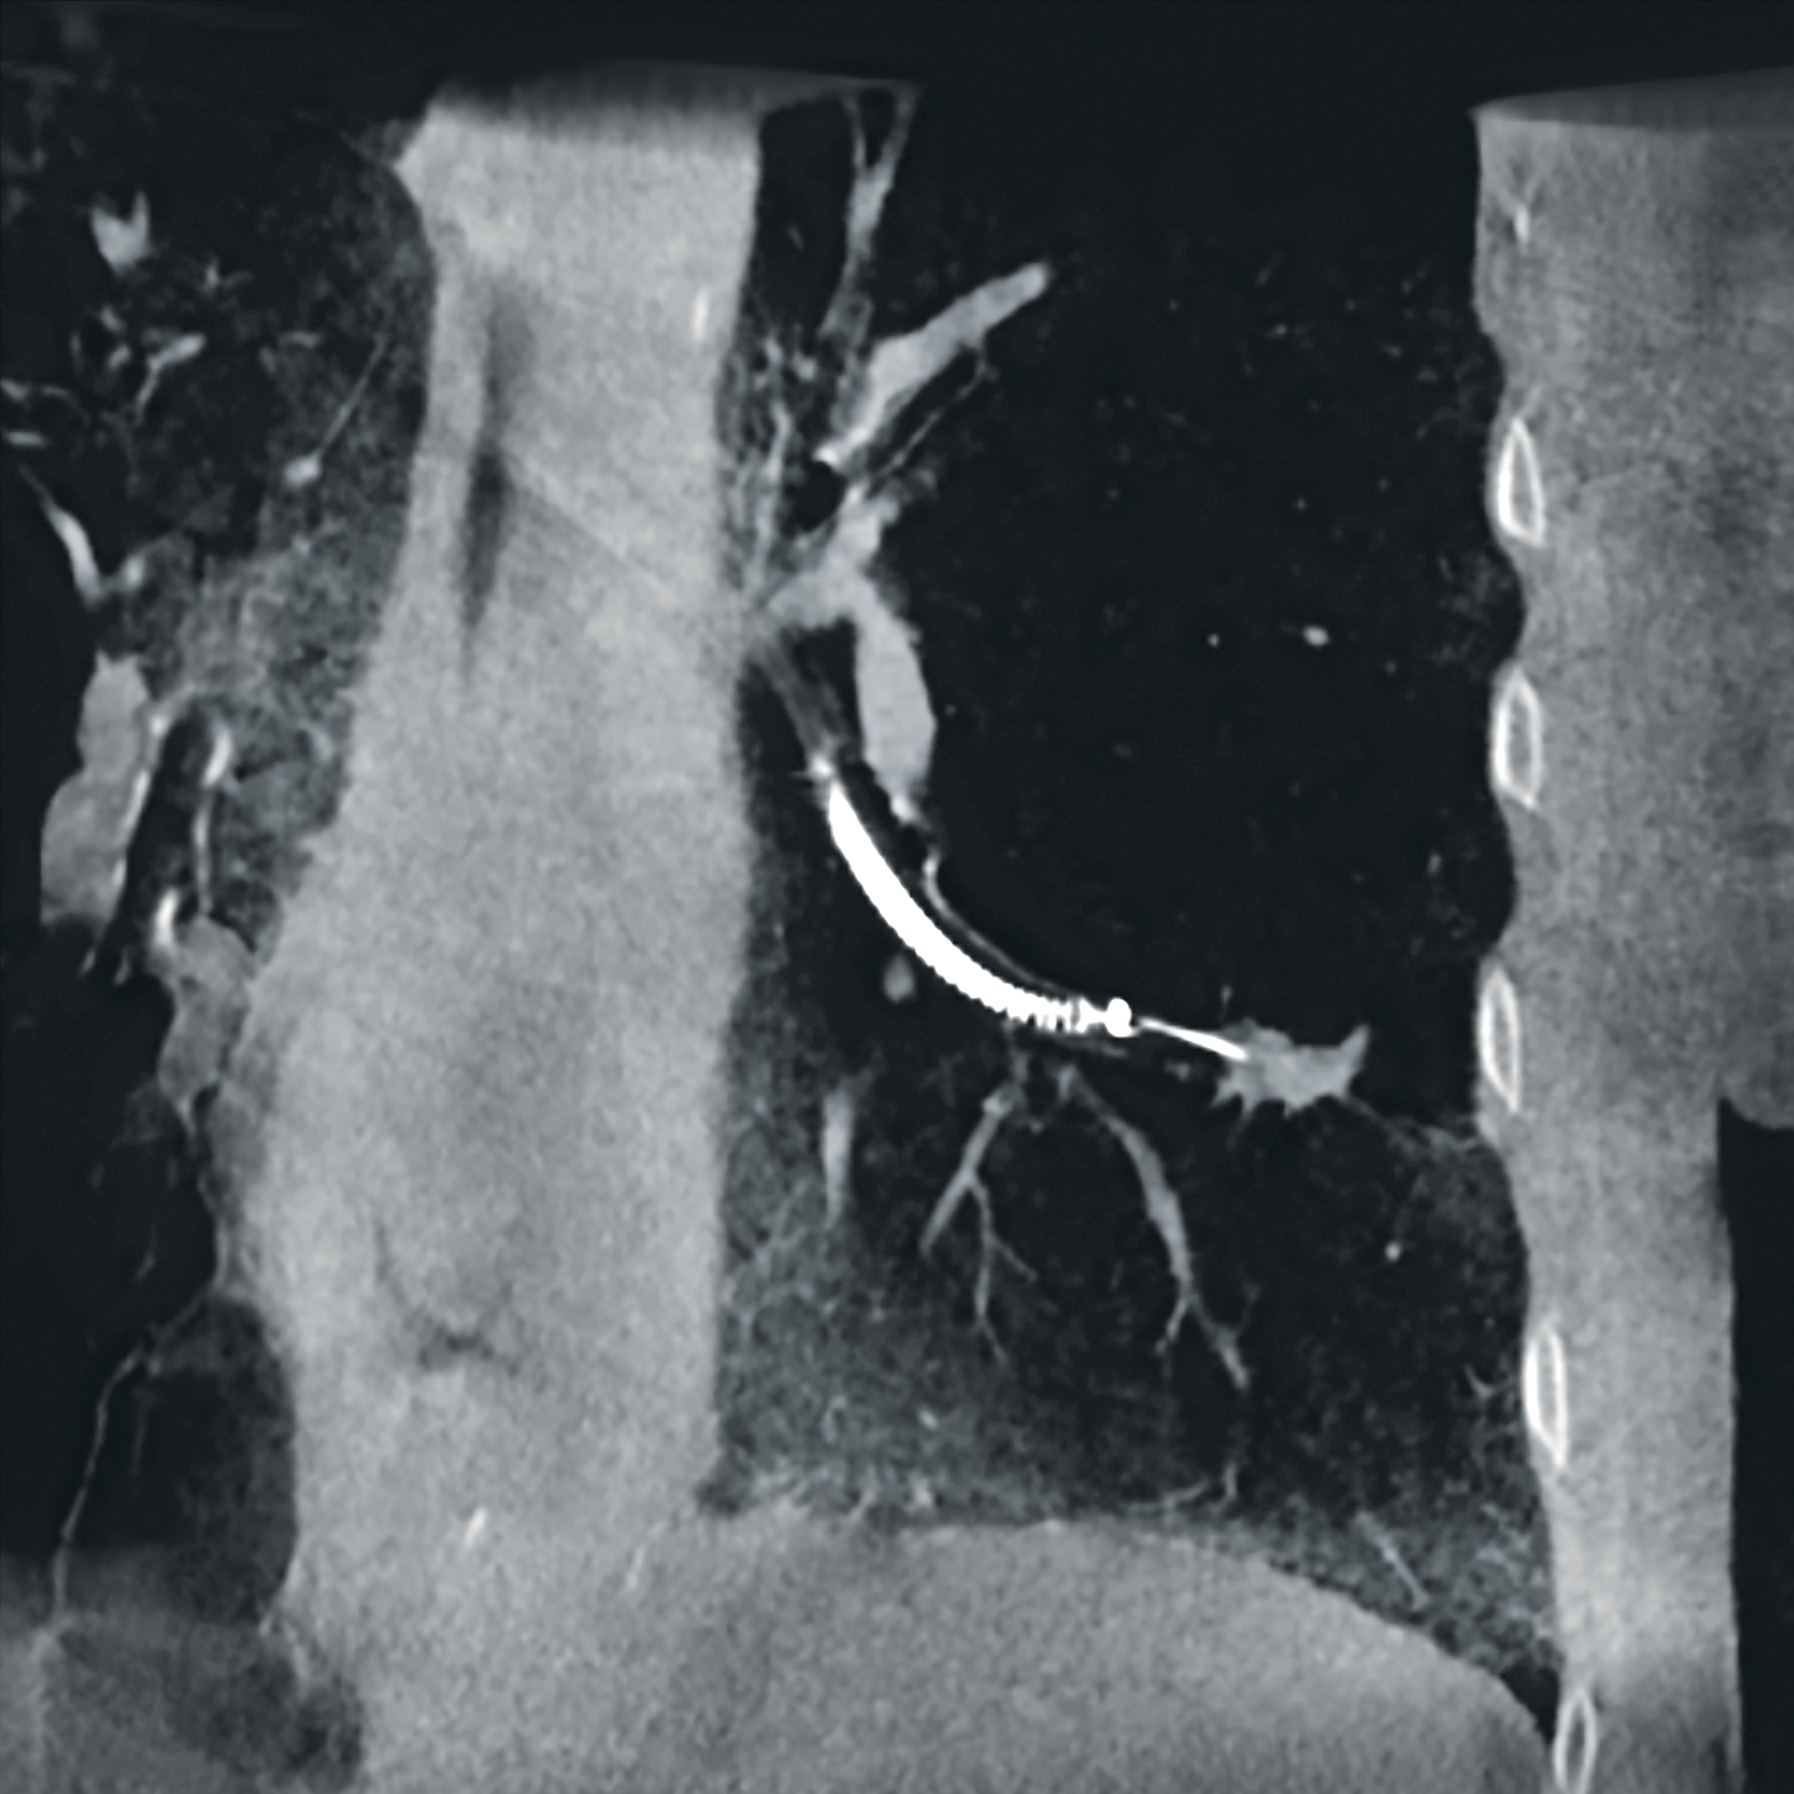

Chirurgie vasculaire

Galerie d'images